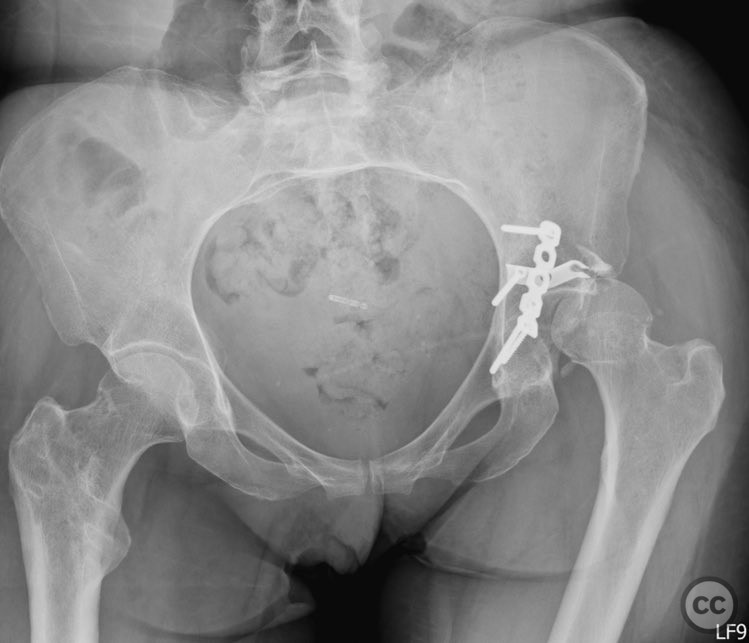

Anatomical surgical approach:  A standard Kocher-Langenbeck approach was performed with a longitudinal incision centered over the greater trochanter, extending proximally along the axis of the gluteus maximus and distally along the femoral shaft. The gluteus maximus was split in line with its fibers, and the short external rotators were detached from their femoral insertions and retracted medially to expose the posterior column and wall of the acetabulum. The sciatic nerve was identified and protected throughout. A distractor was applied across the hip joint to facilitate joint distraction and removal of intra-articular fragments. Impacted articular fragments were elevated, and defects were grafted with ground allograft. Posterior wall fragments were anatomically reduced and stabilized with a combination of plates: a lateral reconstruction plate, a standard buttress plate, and a custom spring hook plate fashioned from a third tubular plate with tines contoured to engage the cortical surface of the posterior wall fragment. The central hole of the spring hook plate was filled first to provide spring tension, followed by fixation of the medial hole to secure the implant.

The injury demonstrated extensive comminution and impaction of the posterior wall with intra-articular debris requiring meticulous removal and elevation. The use of a distractor facilitated both exposure and removal of loose articular fragments. The peripheral comminution necessitated augmentation with a custom spring hook plate to maintain reduction of small cortical fragments not amenable to standard buttress plating. Proper placement of the lateral reconstruction plate overlying the spring hook plate was critical for maintaining fixation integrity; malpositioning resulted in early fixation failure in a comparative case due to bending of the unsupported spring hook implant.

Orthopaedic implants used:   3.5 mm reconstruction plate, standard buttress plate, custom spring hook plate (fashioned from third tubular plate), ground allograft